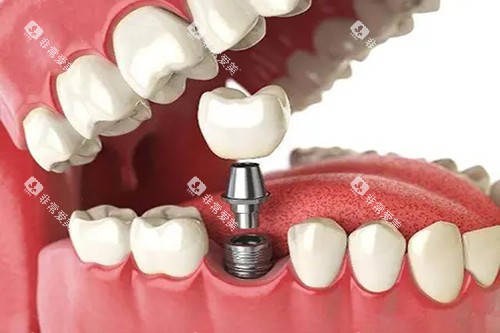

如智能化口腔全景机,能够快速、比较准地获取口腔超全影像,为医生的诊断提供清晰、详细的依据;靠前的种植牙系统,确保种植牙手术的更准一些性和可靠性;舒适的牙科综合治疗椅,让患者在治疗过程中感受到更多的舒适和便利。

在种植牙领域,医院的医生凭借过关的技术和丰富的经验,成功为众多缺牙患者种上了新牙,修养了患者的咀嚼功能和美观。